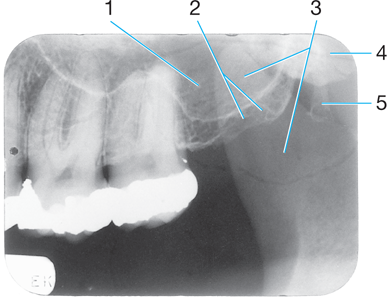

Identify #1.

Border of maxillary sinus

Identify #5.

Lateral pterygoid

Identify the air space image #2

nasopharyngeal

Intersection of the maxillary sinus & the nasal cavity

as viewed on a dental radiograph.

Inverted Y

J or U shape located above the maxillary first molars.

zygomatic process of maxilla #4

Radiopaque